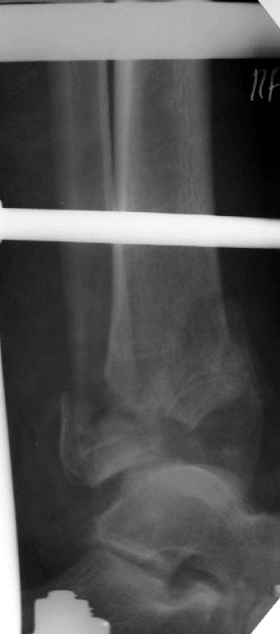

Перелом 43С

Поступил больной 57 лет 14.06.04 в наше отделение. Простой перелом малоберцовой кости Взрывной перелом дистальных отделов болыпеберцовой кости,

Вколоченный перелом дистальных отделов большеберцовой кости. Проводим репозицию с помощью скелетного вытяжения, перед операцией. Думаем как собрать б/б кость? Какой доступ использовать? Может сразу первичный артродез? Как то в форуме говорилось о доступе через м/б кость для артродеза. Возможно ли его использовать в данном случае? Если кто-то его использует, может поделится информацией, как правильно его делать? Сергей Зырянов НСО г Куйбышев.ЦРБ